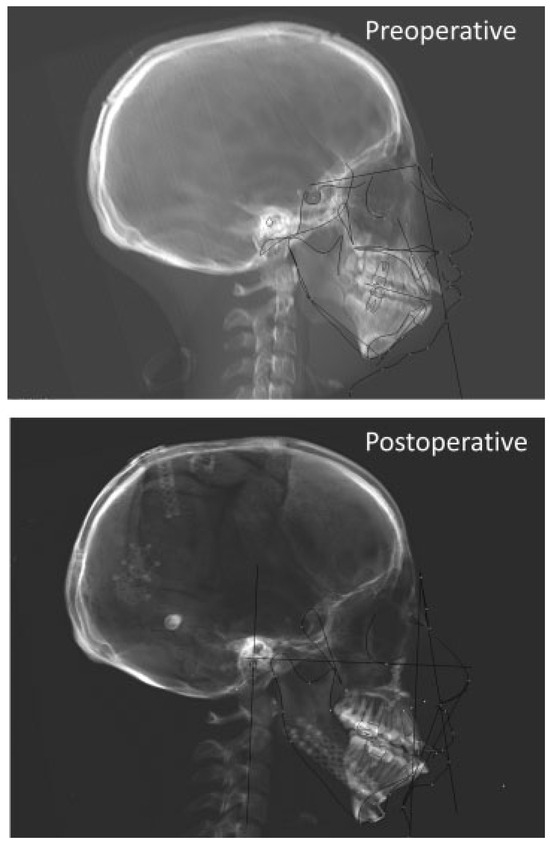

Preoperative and postoperative cephalometric analysis was performed digitally using Dolphin imaging software (Dolphin Imaging & Management Solutions, Chatsworth, CA). Standard cranial, maxillary, mandibular, and dental landmarks were identified in the usual fashion. An appropriate analysis was performed to determine the change in craniofacial relationships postsurgically.

The hallmark dysmorphology of TCS is well described. The goal of cephalometric analysis in this patient population is to quantify the powerful changes that can be made with maxilla-mandibular surgery with regard to both function (airway and occlusion) and overall facial harmony. Preoperative analysis revealed the usual craniofacial abnormalities associated with TCS (Figure 6, Table 2). Preoperative lateral cephalometric analysis revealed maxillary deficiency in the anterior-posterior dimension as well as the vertical dimension when compared with the cranial base (sella–nasion–A angle [SNA], posterior nasal spine to nasion [PNS to N]). The mandible was also globally deficient in most vectors. There were both mandibular body and ramus height deficiencies (gonion to pogonion [Go to Pg] and anterior nasal spine to gonion [ANS to Go]). There was also a significant difference between the position of the maxilla and the mandible (A–nasion–B angle [ANB]). Postsurgically, there was significant return-to-normal values of the maxilla and the mandible when compared with the cranial base (sella–nasion–B angle [SNB] and SNA), with a better balance between the two structures (ANB). Mandibular body length was also lengthened to a more normal value. Utilization of the bilateral sagittal split for the mandible did not have significant effects on the ramus height of the mandible. There was no significant change in the occlusal plane measurements as well as the posterior/ anterior facial heights.

Figure 6.

Cephalometric images pre- and postoperatively showing an improvement in mandibular body length and an improvement in positions of maxilla and mandible.